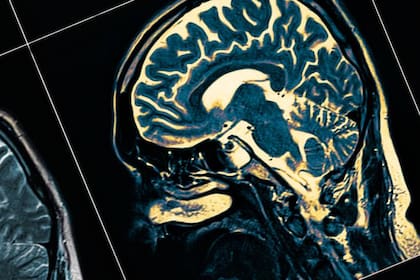

Las ondas cerebrales durante la muerte se ven de la misma forma que cuando uno sueña, medita o recuerda; neurocientíficos de la Universidad de Louisville develaron lo que pasa por la mente antes del deceso

Un grupo de investigadores estadounidenses descubrió que cuando morimos, nuestras ondas cerebrales se ven de la misma manera que cuando soñamos, meditamos o recordamos, lo que significaría que el cerebro permanece activo y coordinado durante y después de la muerte.

Neurocientíficos de la Universidad de Louisville, en Estados Unidos, analizaron las ondas cerebrales de un hombre de 87 años con epilepsia, a quien le realizaban una electroencefalografía cuando este sufrió un ataque al corazón y murió. Durante este evento inesperado, pudieron registrar la actividad de un cerebro moribundo por primera vez.